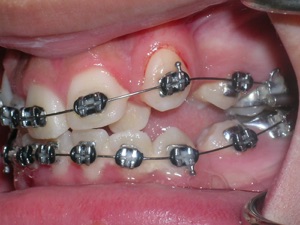

First Premolars were removed. We used an anchor device on the top jaw known as a “Nance” holding arch to help us retract the canines into the first premolar space. The holding device is used to reduce shifting of the top back teeth forward.